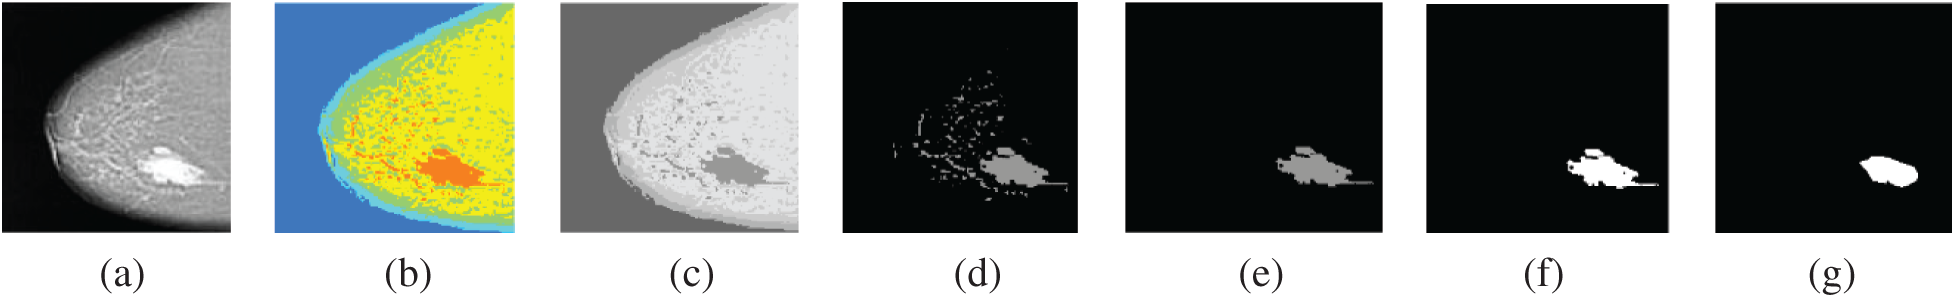

Finally, the third experiment is performed to evaluate the proposed segmentation algorithm of breast cancer lesions. The results on MLO and CC images are shown in Figs. 13 and 14, respectively.

Figure 14: Segmentation of breast cancer lesions in a CC image (a) Original image (b) RGB image (c) Gray-scale image (d) Segmented image (e) ROI image (f) Tumor image (g) Reference image